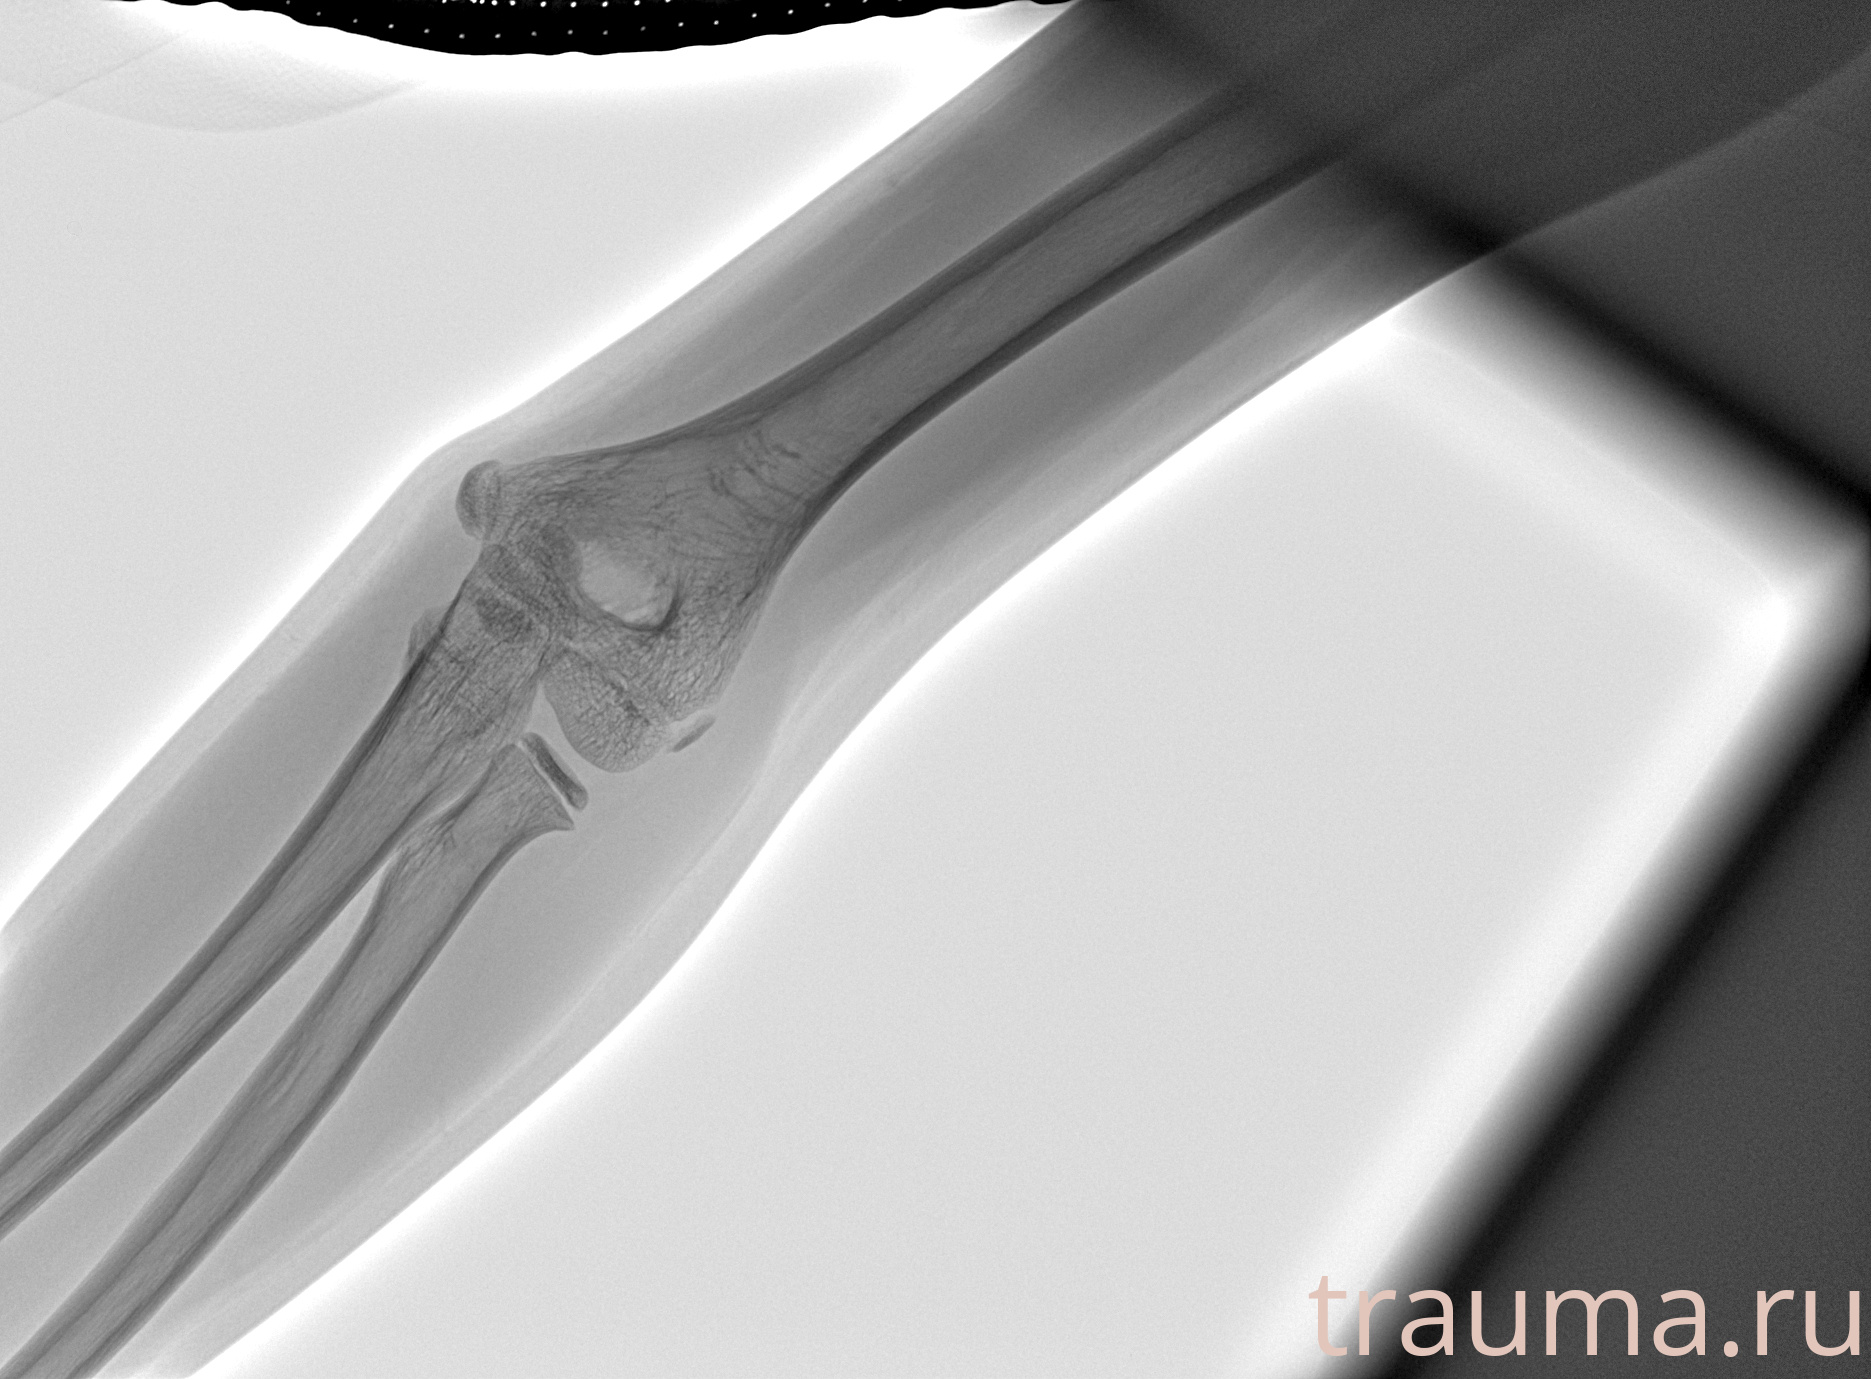

Рентген на дому: по вашему адресу приезжает врач-рентгенолог, травматолог-ортопед с мобильным рентгеновским аппаратом, проводит диагностику травмы или заболевания, делает необходимые рентгенограммы, дает рекомендации по дальнейшему лечению. Получить качественные снимки в домашних условиях возможно благодаря уникальной методике, разработанной МосРентген Центром для института  Склифосовского